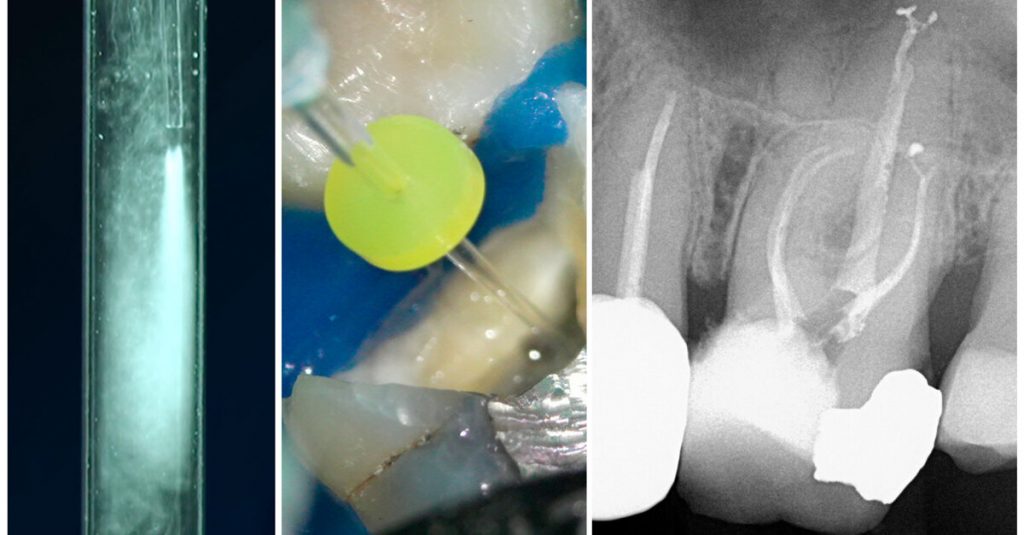

First Odne Summit marks the successful completion of the priority access programme for OdneClean

GETTYSBURG, Pa., US: The Swiss medical device startup Odne just recently held its first online summit to disseminate new scientific and clinical knowledge about the company’s Root Preservation Therapy. The focus of the event was OdneClean, an advanced debridement device that produces hydrodynamic cavitation and employs a saline solution as the main irrigant. The summit […]